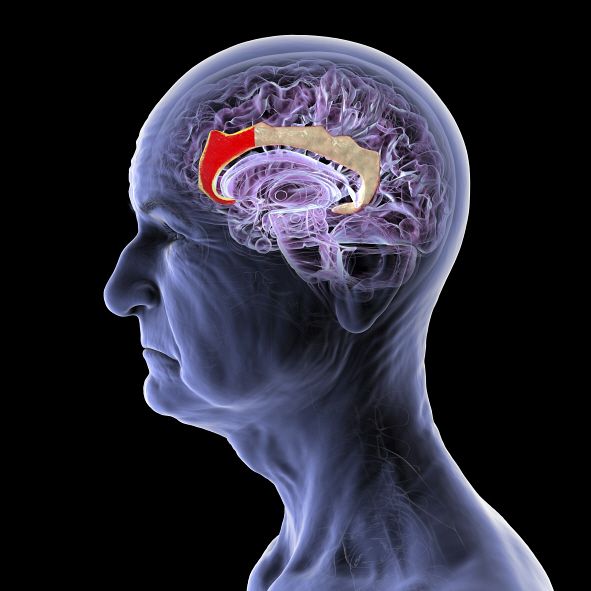

NeuroLix, a Chinese startup, is developing a groundbreaking brain-computer interface technology that promises to revolutionize the way we interact with computers and other devices. What sets NeuroLix apart from other companies in the field is that their technology does not require any surgical implants, making it non-invasive and accessible to a larger population.

The traditional BCI technology often involves implanting electrodes directly into the brain, which poses risks and limitations. NeuroLix’s approach, on the other hand, uses a combination of advanced sensors and machine learning algorithms to decode brain signals from outside the skull.

This new approach has the potential to open up a whole new world of possibilities, from controlling devices with our thoughts to enhancing communication for individuals with disabilities. The technology could also have applications in healthcare, gaming, and virtual reality.

NeuroLix is currently conducting trials to fine-tune their technology and make it more accurate and reliable. The company is working closely with neuroscientists and experts in the field to ensure that their product meets the highest standards of safety and efficacy.

While there is still much work to be done before NeuroLix’s BCI technology becomes commercially available, the potential impact it could have on society is immense. The technology has the power to transform how we interact with the digital world and unlock new capabilities we never thought possible.

As NeuroLix continues to push the boundaries of what is possible with brain-computer interfaces, the future looks bright for this Chinese startup. With their innovative approach and dedication to creating a non-invasive solution, NeuroLix is poised to make a significant impact on the field of neuroscience and technology.